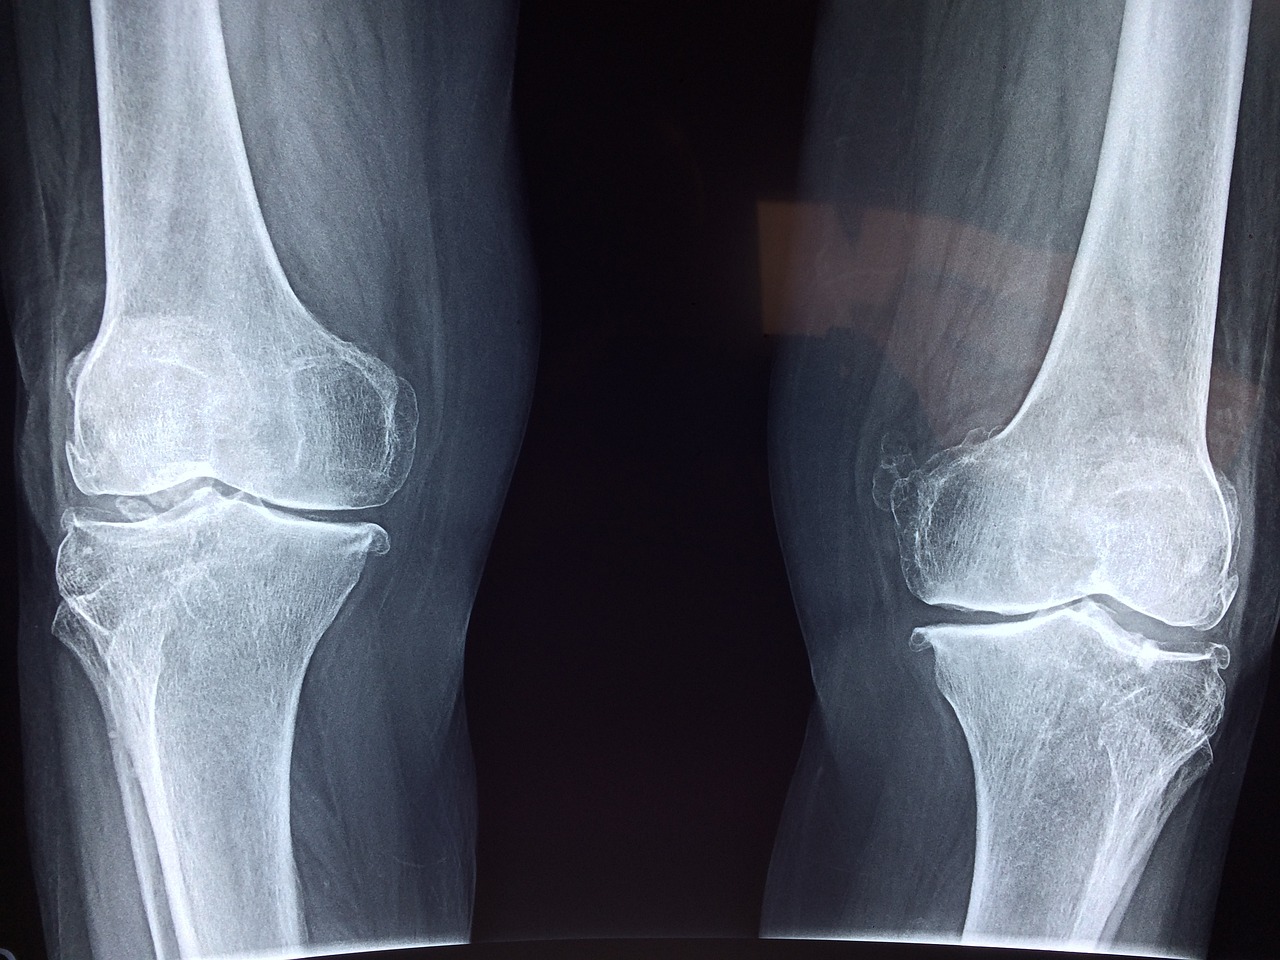

체중 증가와 관절 건강은 밀접한 연관성이 있습니다. 체중이 증가하면 관절에 가해지는 압력이 커지면서, 특히 무릎과 엉덩이 관절이 영향을 받습니다. 이는 관절염과 같은 만성 질환의 위험을 높이며, 관절 통증과 변형을 초래할 수 있습니다. 과도한 체중은 관절의 마모를 가속화하고, 관절의 기능을 제한하는 요인이 됩니다.